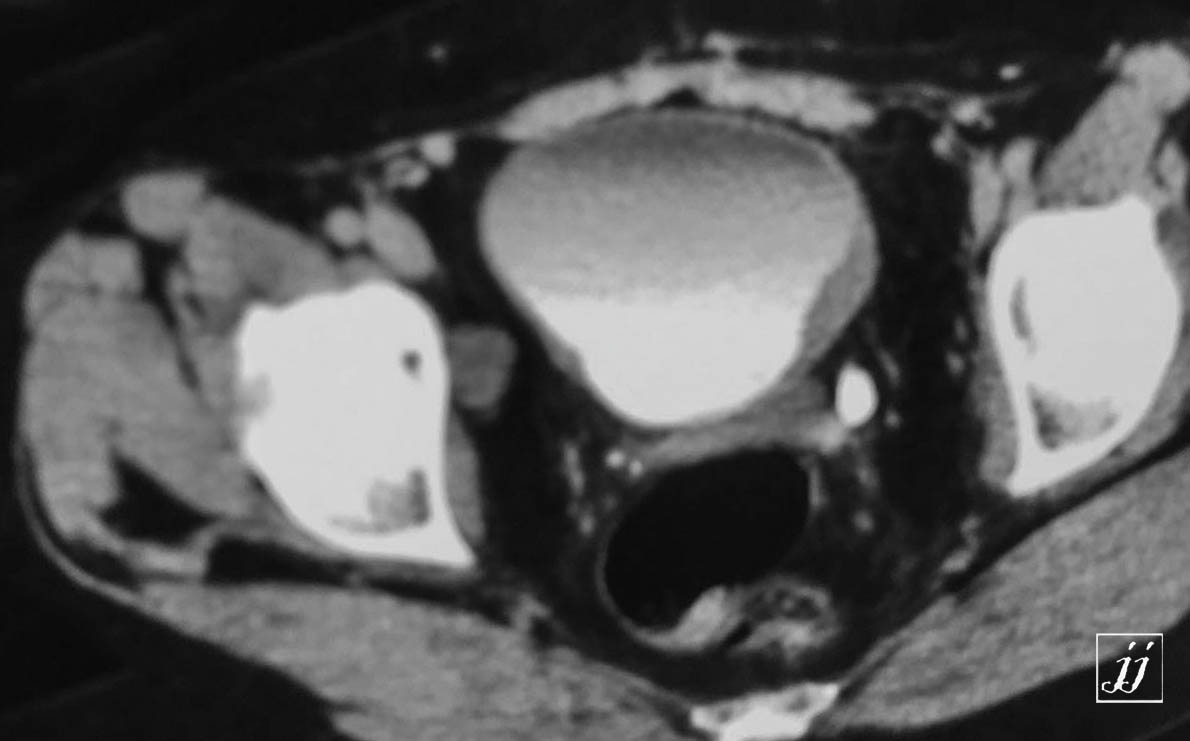

Abdomen- urinary bladder tumor and left hydronephrosis (6)